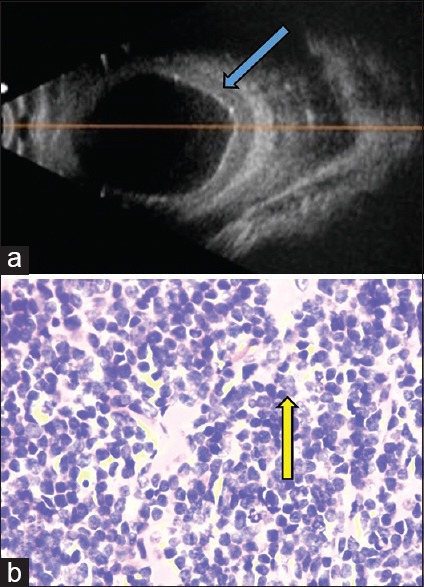

A 5-year-old boy presented with gradually progressive painful proptosis of the left eye for 5 months. He had an incidental testicular swelling for which he underwent high inguinal orchidectomy and histopathology showed atypical lymphoid cells. His vision was 6/6, N6 in the right eye, and no perception of light in the left eye. Left eye examination revealed an inferior dystopia and total ophthalmoplegia with corneal exposure changes. A computerized tomography scan showed an isodense mass molding around the globe. An incision biopsy from the subconjunctival mass showed atypical large lymphocytes on histopathology which on immunohistochemistry confirmed a diagnosis of precursor B-cell lymphoblastic lymphoma (B-LBL). Bone marrow aspiration and biopsy were normal. The patient was started on oral steroids and high-risk acute LBL chemotherapy protocol to which he showed excellent response. Precursor B-LBL is a rare neoplasm of the pediatric and adolescent age group. A total of 22 cases involving the orbit have been reported to date of which 17 belonged to the pediatric age group. Early detection and prompt initiation of multiagent chemotherapy have shown good survival rates in these patients.